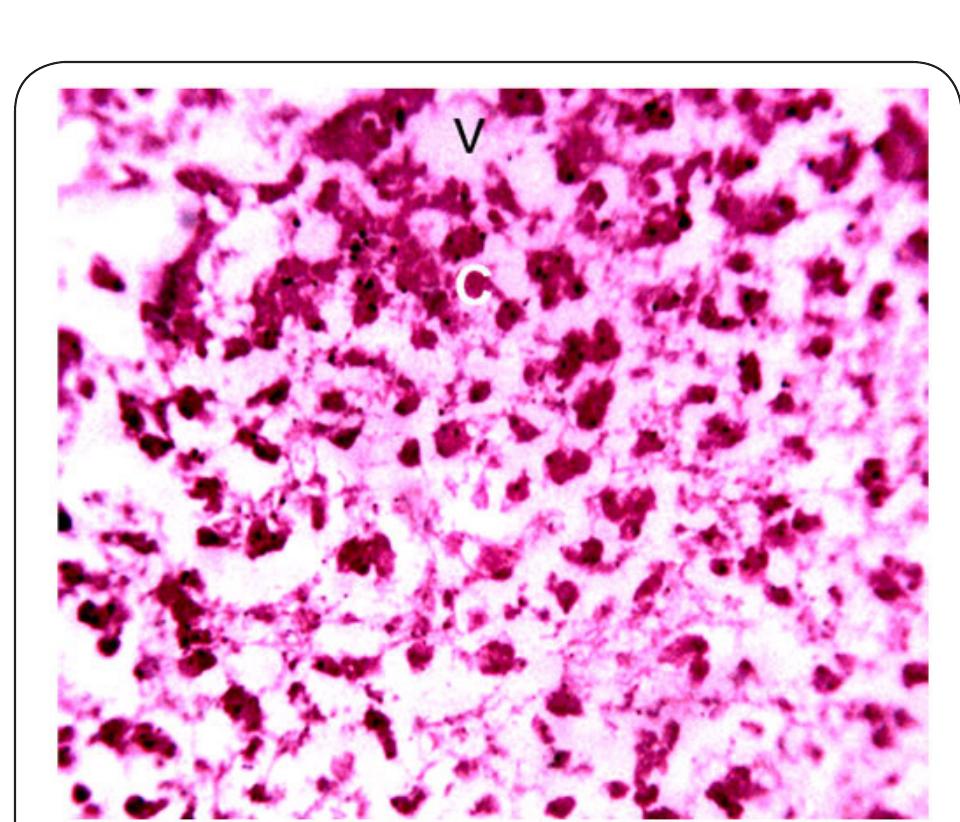

Dr. Ozovehe Patrick Samuel - FEDERAL UNIVERSITY OF TECHNOLOGY, MINNA-NIGERIA